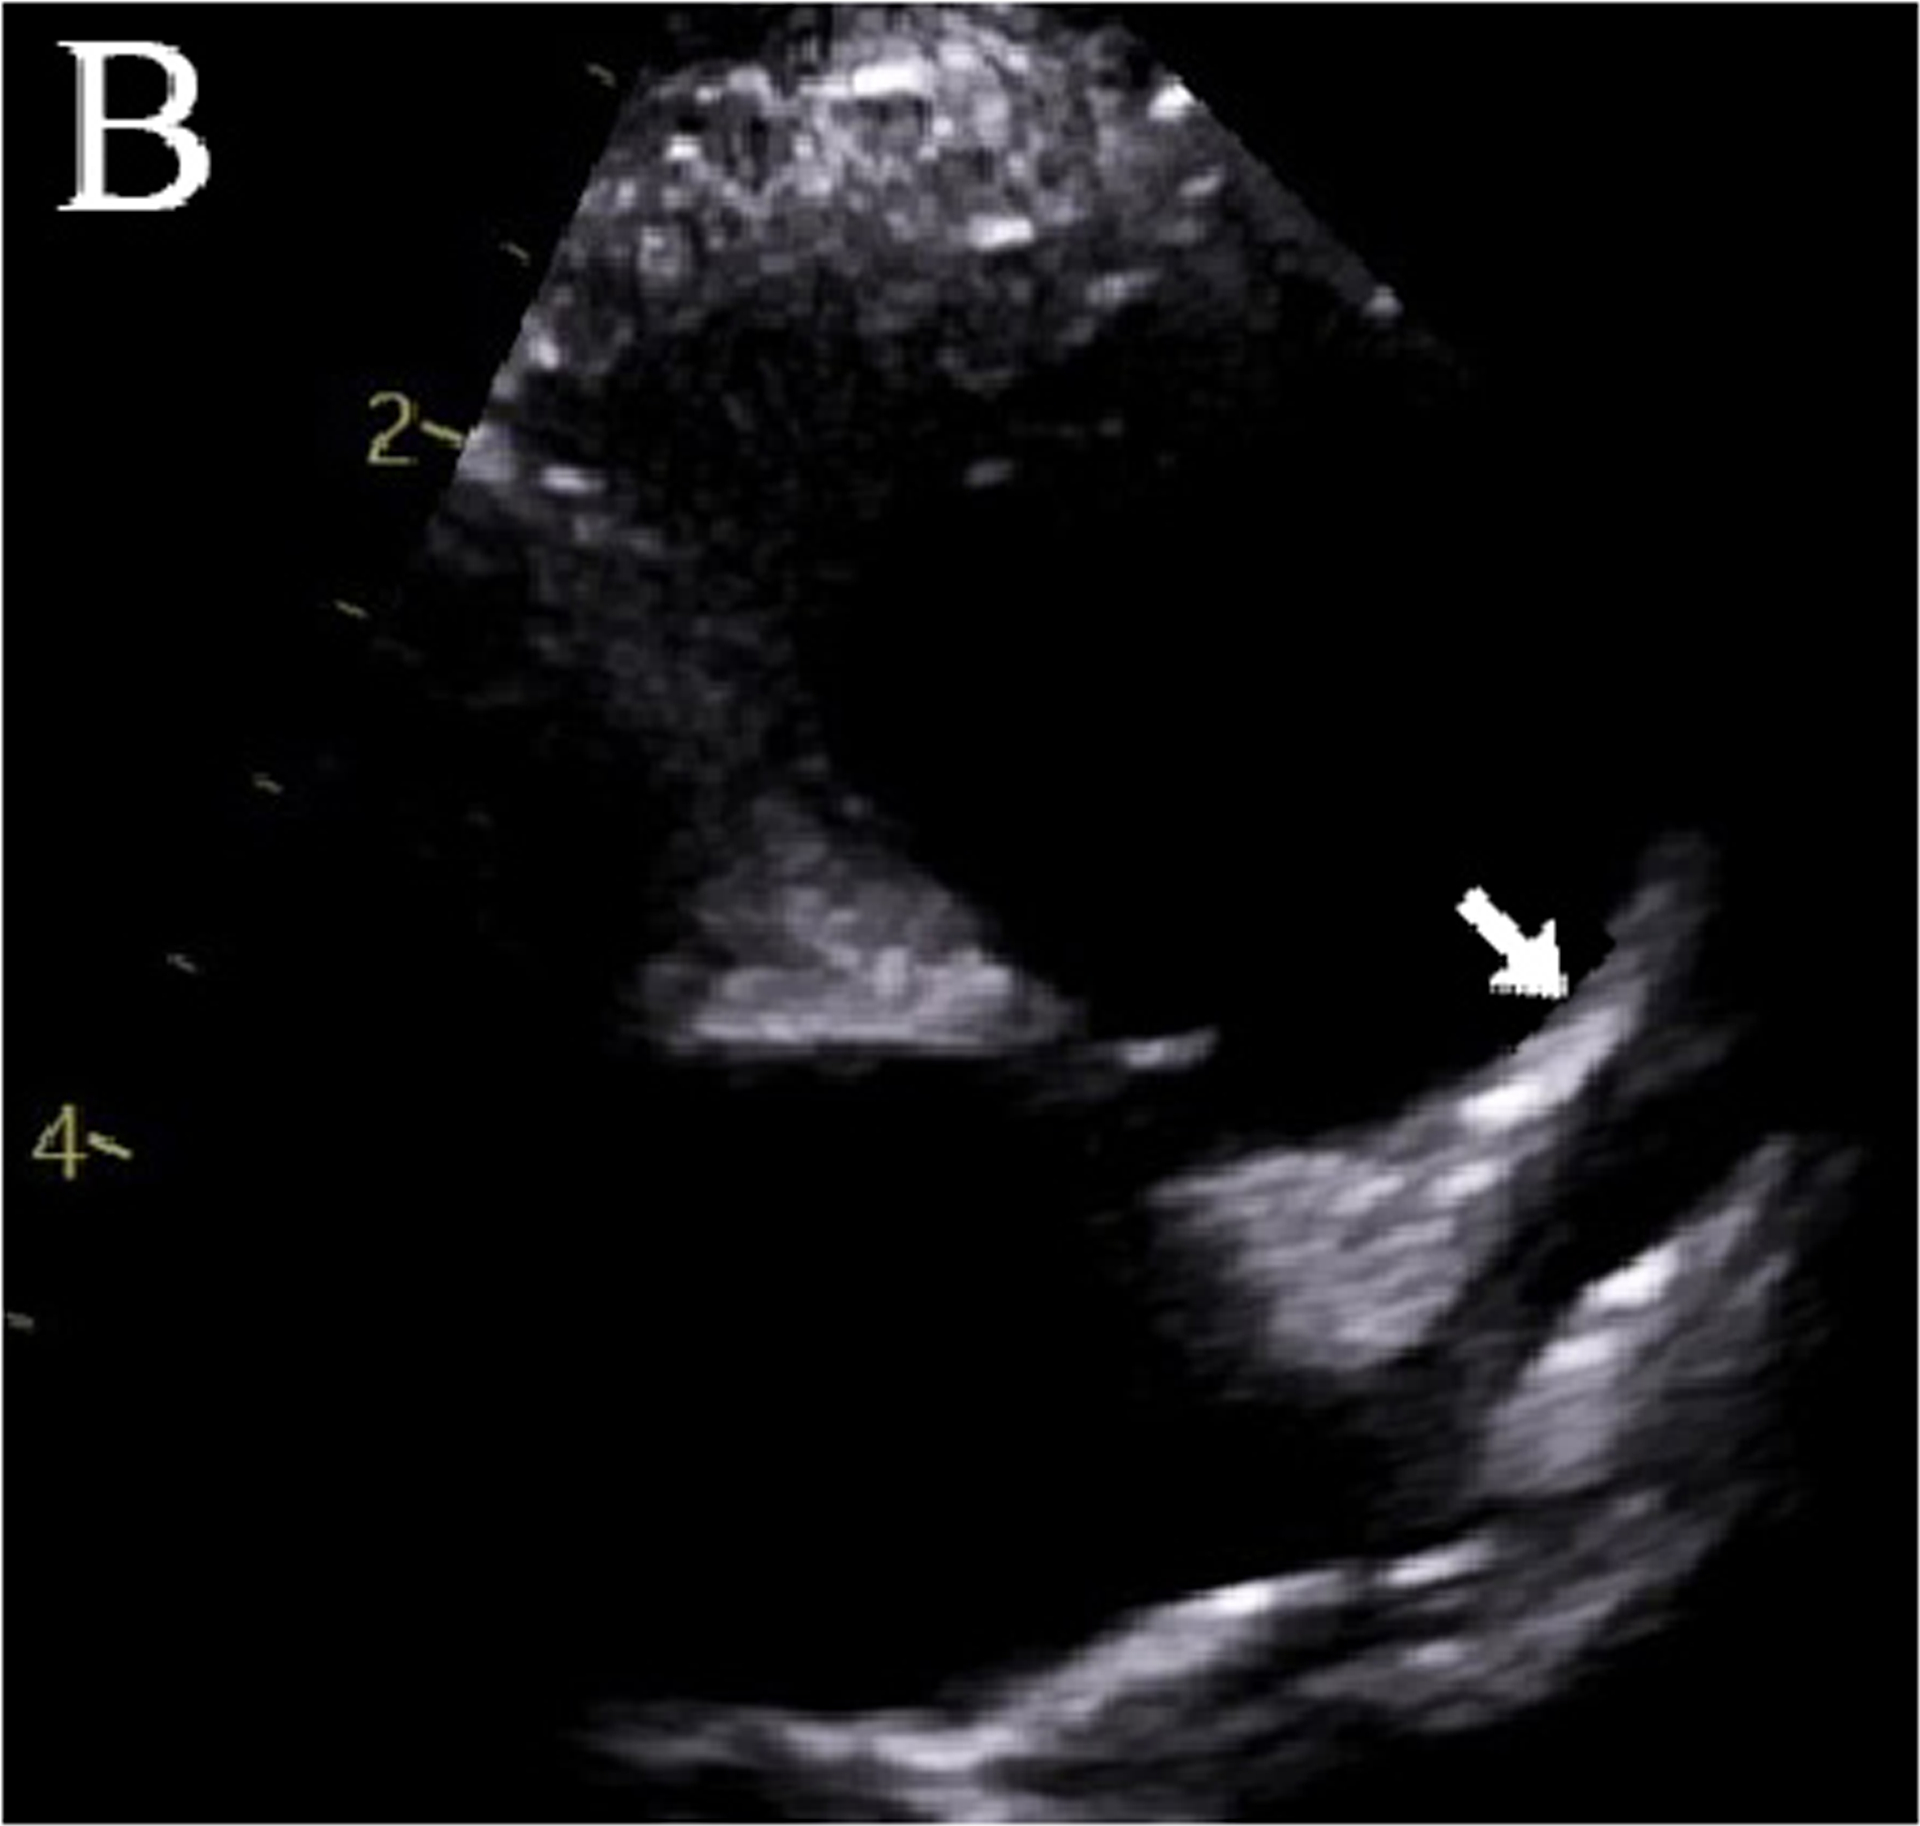

A 5-year-old boy had onset of MIS-C symptoms 55 days after COVID-19 illness and 15 days after receiving his first BNT162b2 COVID-19 vaccination. He was admitted three times for MIS-C, twice after his steroid dose was tapered. On his initial admission, he was given intravenous immunoglobulin (IVIG) and steroids. During his second admission, new, moderate coronary dilation was noted, and he was treated with IVIG and steroids. At his last admission, worsening coronary dilation was noted, and he was treated with infliximab and steroids. During follow-up, he had improvement in his coronary artery dilatation. However, his inflammatory markers increased after steroid wean, and his steroid taper was further extended, after which time his inflammatory markers improved. This is the only such reported case of a patient who was admitted three times for MIS-C complications after Covid-19 vaccination.